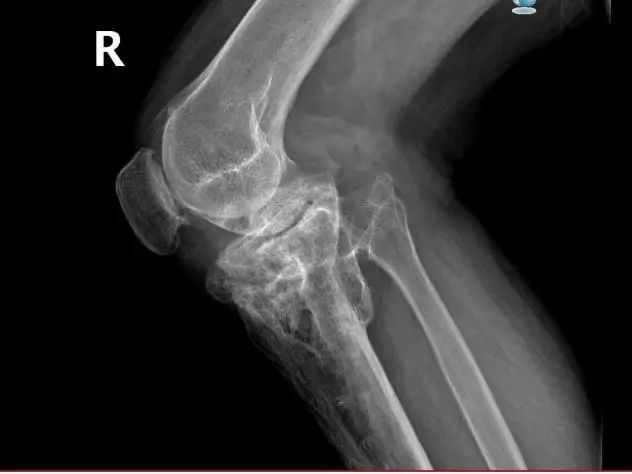

58岁的尤大叔是晋江内坑人,9年前因外伤导致右侧胫骨近端骨折,在外院进行手术治疗。但术后恢复欠佳,尤大叔行走状况逐渐受限,右膝关节严重外翻,因经济原因一直未进行系统治疗,生活、工作上带来的不便让他苦不堪言。

▲严重外翻畸形

▲术前影像